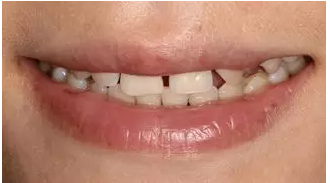

術(shù)前微笑照

術(shù)后微笑照